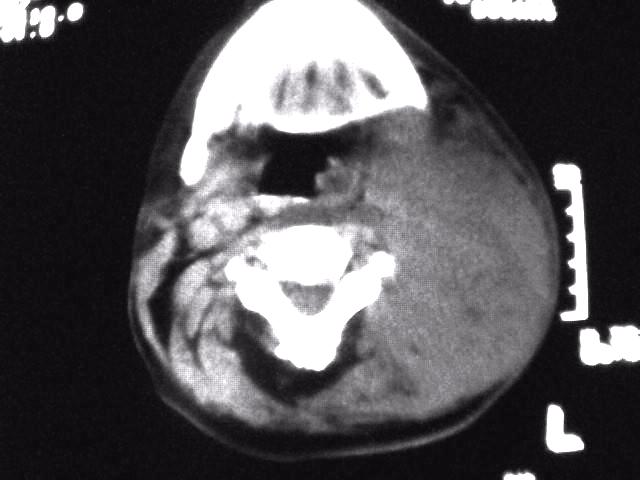

颈部层厚10mm间距10mm连续扫描及增强扫描共24层示:左侧下颈部胸锁乳突肌内侧区域内可见多发软组织结节,密度不均,内可见斑片状低密度区,大小不等,部分融合成块,左侧融合成一块者大约9.0x5.4,与周围肌肉、血管等结构界面不清,骨质未见明显浸润影。左侧锁骨下可见多个软组织结节,与周围界限尚清,左侧锁骨上窝内可见一大软组织肿物,大小约4.7x3.7cm,内密度欠均匀中心可见低密度区。

考虑:左侧颈部及双侧锁骨下多发淋巴结肿。非何杰金氏淋巴瘤可能性大,建议进一步检查。